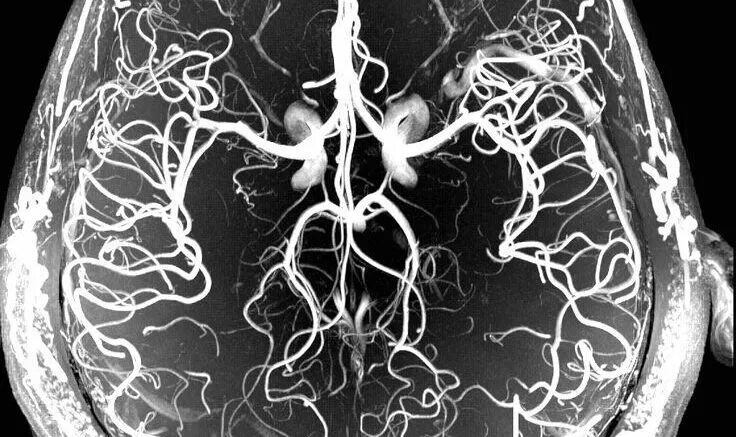

Мрт сосудов головного мозга в туле